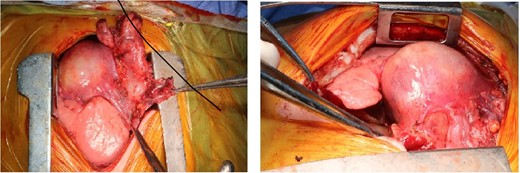

She underwent mediastinal tumor excision, thymectomy and partial pericardectomy through midsternotomy. Pericardium was not reconstructed because small defect around 2 cm.

The mass was attached to pericardium, compressing the right atrium and encased the right phrenic nerve (Fig. 3). The mass en-bloc excision and thymectomy revealed multiloculate well-defined cyst measuring 6 cm in maximum dimension. Upon opening the cyst, and the pericardium yellowish sebaceous and cheesy material was found and identified as ruptured mature cystic teratoma with inflammatory reaction. Microscopy showed a ruptured mature cystic teratoma with inflammatory reaction (showing an unremarkable squamous, respiratory and gastric types epithelium, mature adipose tissue, smooth muscle tissue, and skin adnexa), with an unremarkable thymic tissue and no immature elements or malignancy.